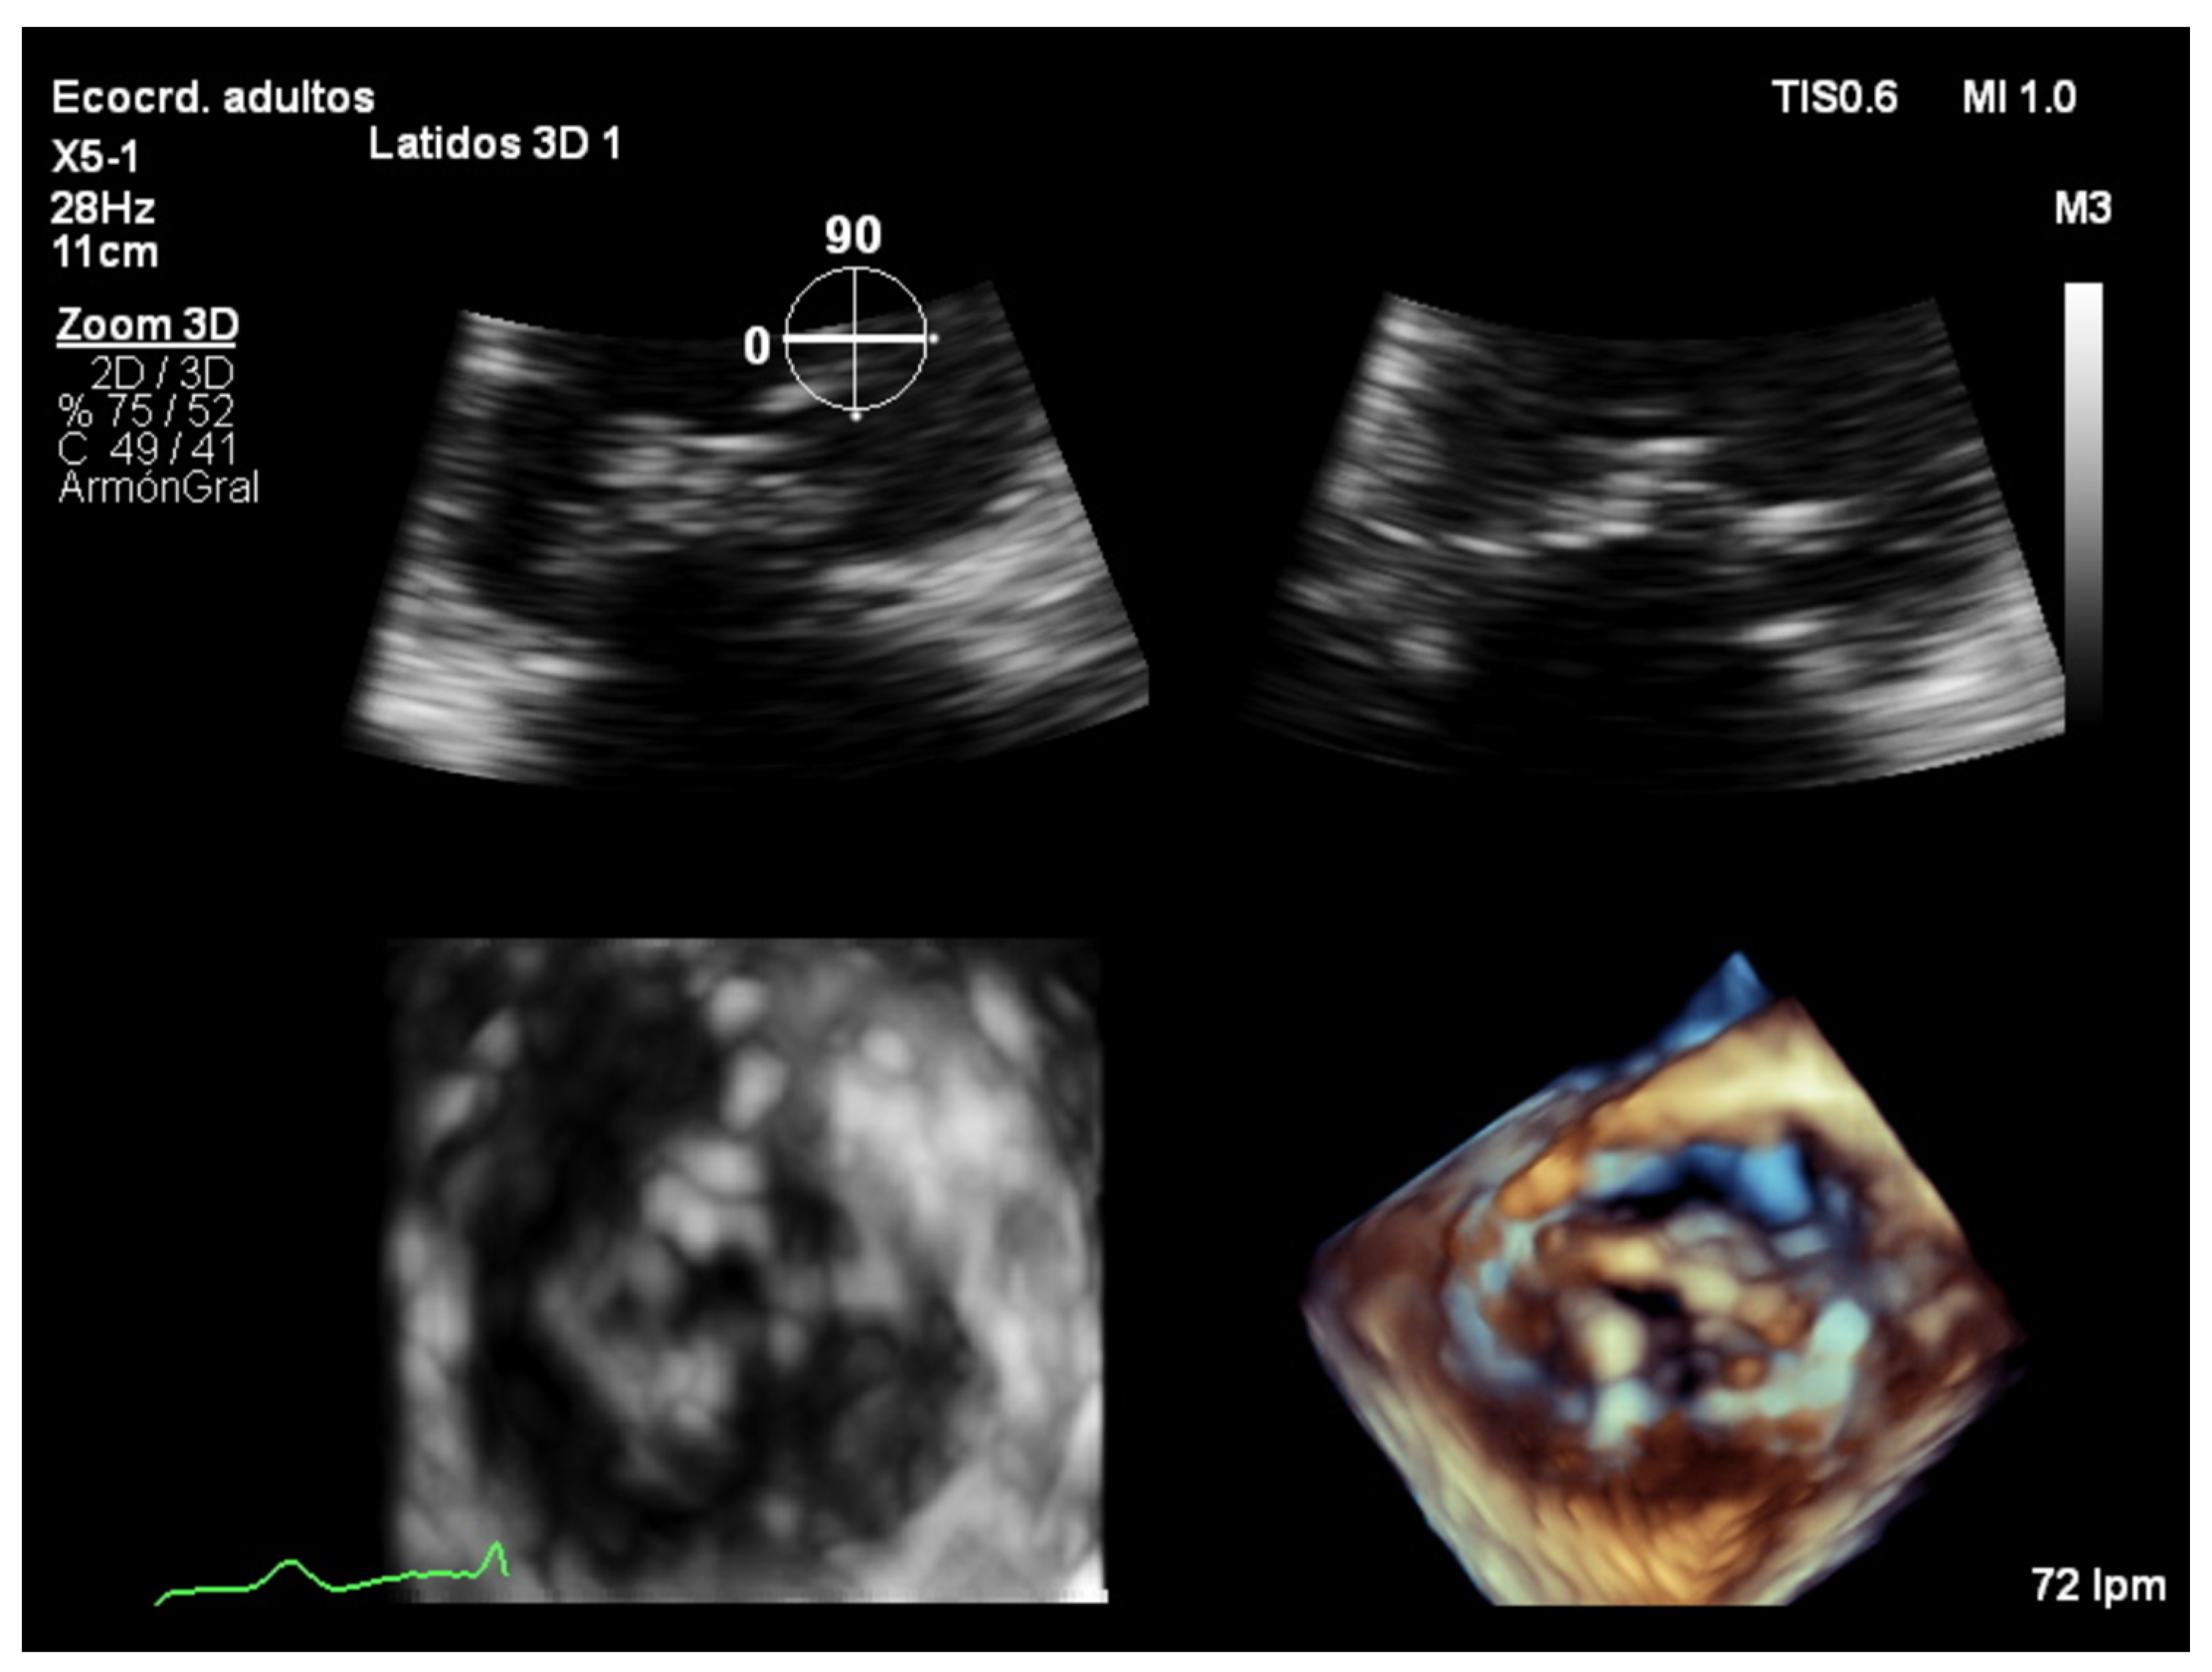

7.3. Real-Time 3D Imaging

7.4. Focused Wide-Sector (3D Zoom) Imaging

- It measures all three spatial dimensions. Therefore, it is not reliant on plane positioning and does not require geometric assumptions of cardiac structures.

- Images can be rotated and viewed from different perspectives. This allows for a better understanding of the relationship between structures and makes 3D images more intuitive.